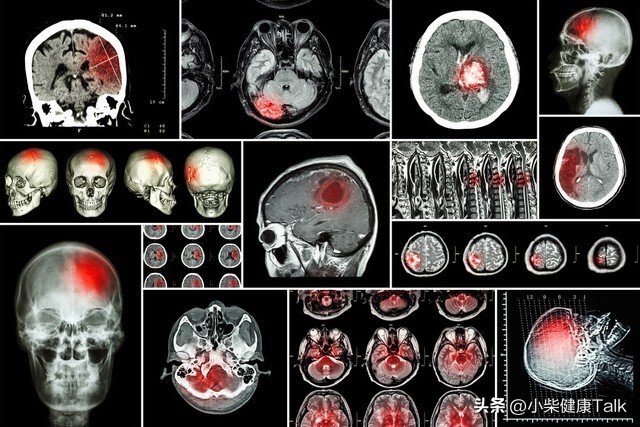

這個故事讓人心頭一緊,天氣變冷,很多人尤其是老年人往往忽視了身體的警鐘。腦梗這種疾病像個隱形殺手,悄無聲息間威脅著健康。那麼,為什麼冬天會成為腦梗的高發季?又有哪兩件事是出門時必須注意的?

冬季氣溫下降,人體的血管會受到寒冷的刺激而收縮。血管一旦變窄,血液流動的速度就會減慢,血液中的雜質更容易堆積在血管壁上,形成血栓。

對於老年人來說,身體的代謝功能減弱,血管的彈性也逐漸下降,血壓波動會更加明顯。高血壓、糖尿病等慢性病患者,血液本身就容易變黏稠,遇到天冷,風險更是成倍增加。稍不注意,血栓脫落或堵塞腦部血管,就會引發腦梗。

醫生經常提到,腦梗的發生並不是一瞬間的,它往往有一些早期信號,比如頭暈、肢體麻木、突然的無力感,甚至是短暫的語言障礙。但很多人因為這些癥狀持續時間短,誤以為是小毛病,等到真的發作時,往往為時已晚。